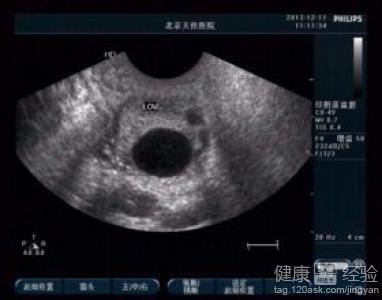

卵泡小排出后能如常怀孕吗

女性是否能够顺利的怀孕,跟身体是否能正常排出卵泡有直接的关系。女性的卵泡壁厚度非常的厚,如果卵泡壁非常薄的话,那么怀孕就不容易成功了。那么,卵泡小排出后能如常怀孕吗?